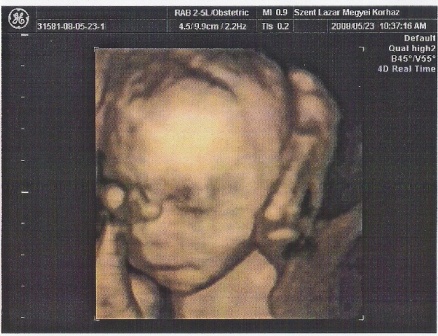

Petra, annyira jók ezek a képek! Hol csinálták?! Hihetetlenül jól látszik Hanna Róza!